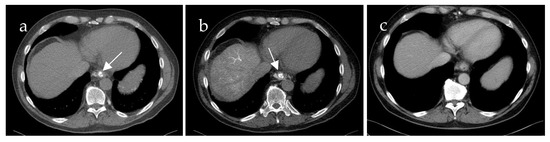

Inflow into esophageal, gastric and small bowel varices differed significantly between patients with PVCT (p = 0.021, p = 0.016 and p = 0.031, respectively) compared to patients without PVCT. In patients with PVCT, esophageal varices were fed solely by the SV in 75% (n = 9, example shown in Figure 3), solely by the mesenteric vein system in 8% (n = 1) and by both systems in 17% (n = 2, example of this rare case shown in Figure 4). Patients without PVCT showed a more equal distribution of inflow hemodynamics: esophageal varices were fed by solely the SV system in 22% (n = 2), by solely the SMV system in 22% (n = 2) and by both systems in 56% (n = 5, example of this is shown in Figure 5). In patients without PVCT, gastric varices were fed by the SV (22%, n = 2), by the SMV (11%, n = 1) or both (22%, n = 2). In contrast, 59% of the patients with PVCT (n = 7) showed gastric varices which were fed only by the SV. In 33% of cases (n = 4), both the SV and SMV drained into gastric varices. No inflow into gastric varices solely from the SMV was detected. These results were statistically significant (p = 0.016).

Figure 3. Computed tomography mesenterico-portography (a) and computed tomography splenoportography (b) of a 58-year-old patient with portal hypertension, portal vein thrombosis and portal vein confluence thrombosis. Esophageal varices (EV) are detected after contrast injection into the splenic artery ((b), white arrow). The EV do not show contrast enhancement after contrast injection into the superior mesenteric artery.